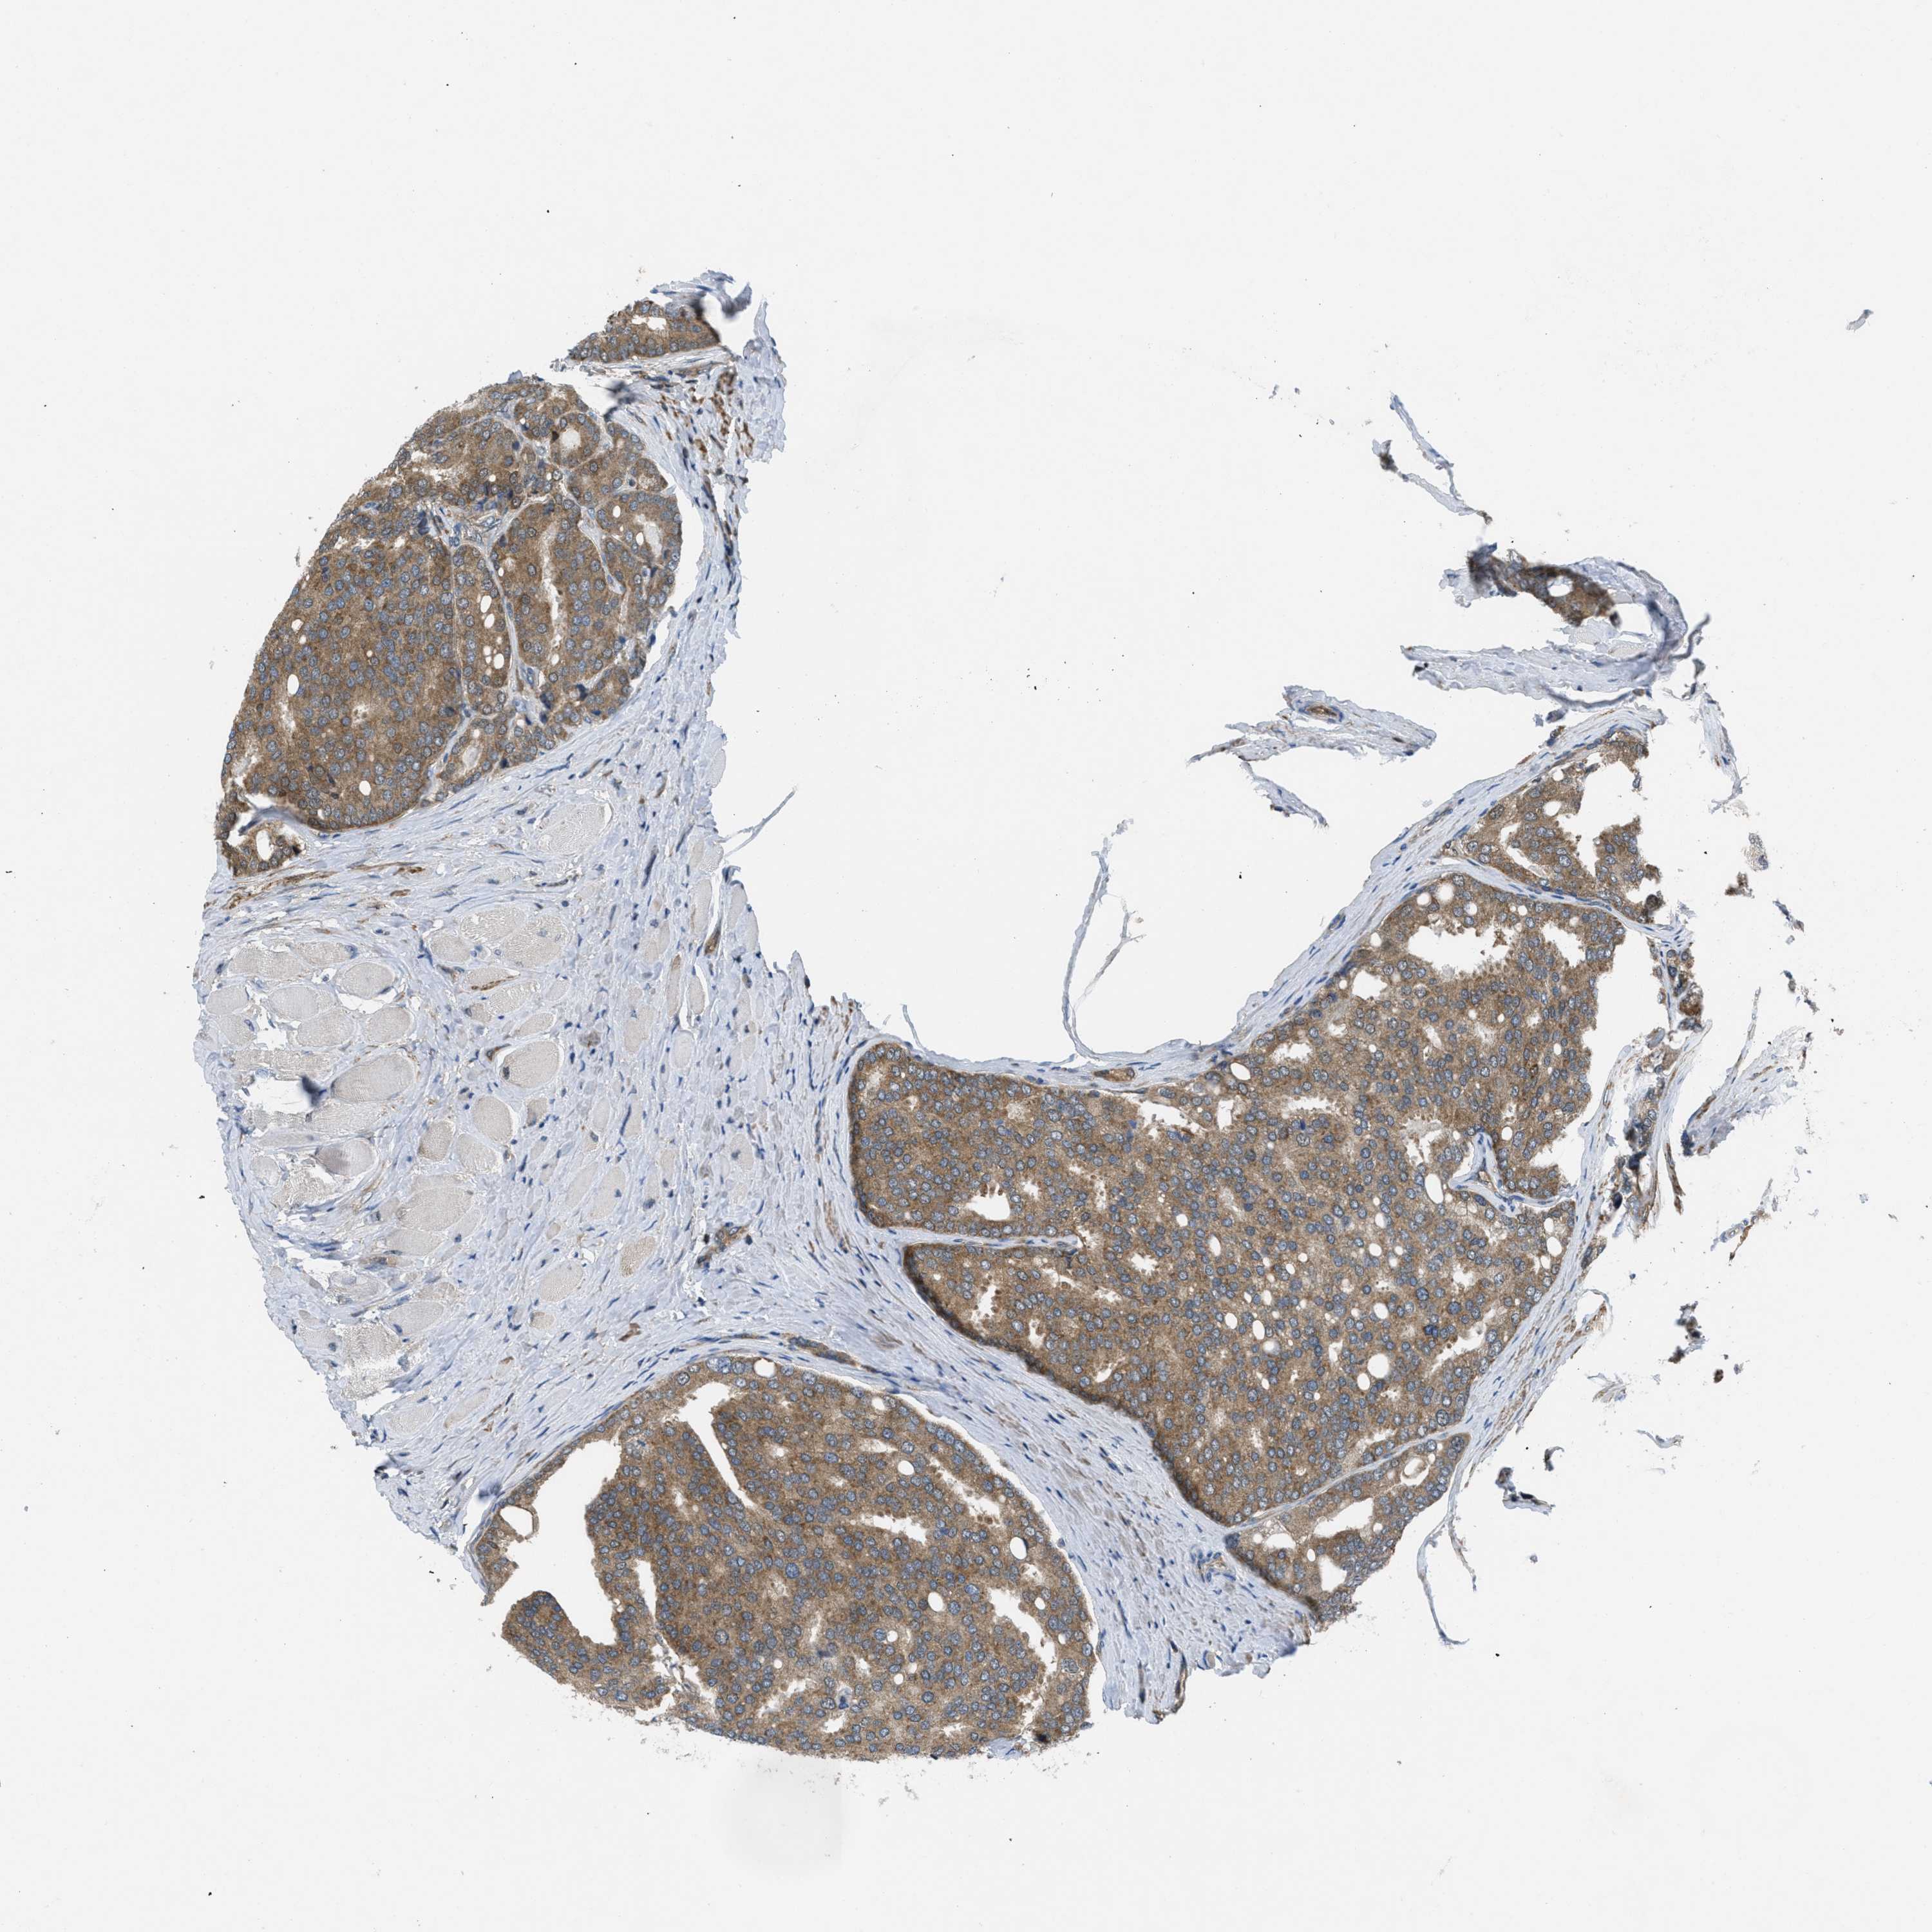

PROSTATE CANCER - Protein expressioni

A mouse-over function shows sample information and annotation data. Click on an image to view it in a full screen mode. Samples can be filtered based on level of antibody staining by selecting one or several of the following categories: high, medium, low and not detected. The assay and annotation is described here.

Antibody stainingi

Antibody staining in the annotated cell types in the current human tissue is reported as not detected, low, medium, or high, based on conventional immunohistochemistry profiling in selected tissues. This score is based on the combination of the staining intensity and fraction of stained cells.

Each image is clickable and will lead to virtual microscopy that enables deeper exploration of all samples and also displays staining intensity scores, fraction scores and subcellular localization as well as patient and tissue information for each sample.

Antibody HPA017168

Staining

High

Medium

Low

Not detected

Intensity

Strong

Moderate

Weak

Negative

Quantity

>75%

75%-25%

<25%

None

Location

Nuclear

Cytoplasmic/membranous

Cytoplasmic/membranous,nuclear

Adenocarcinoma, High grade

Adenocarcinoma, Low grade